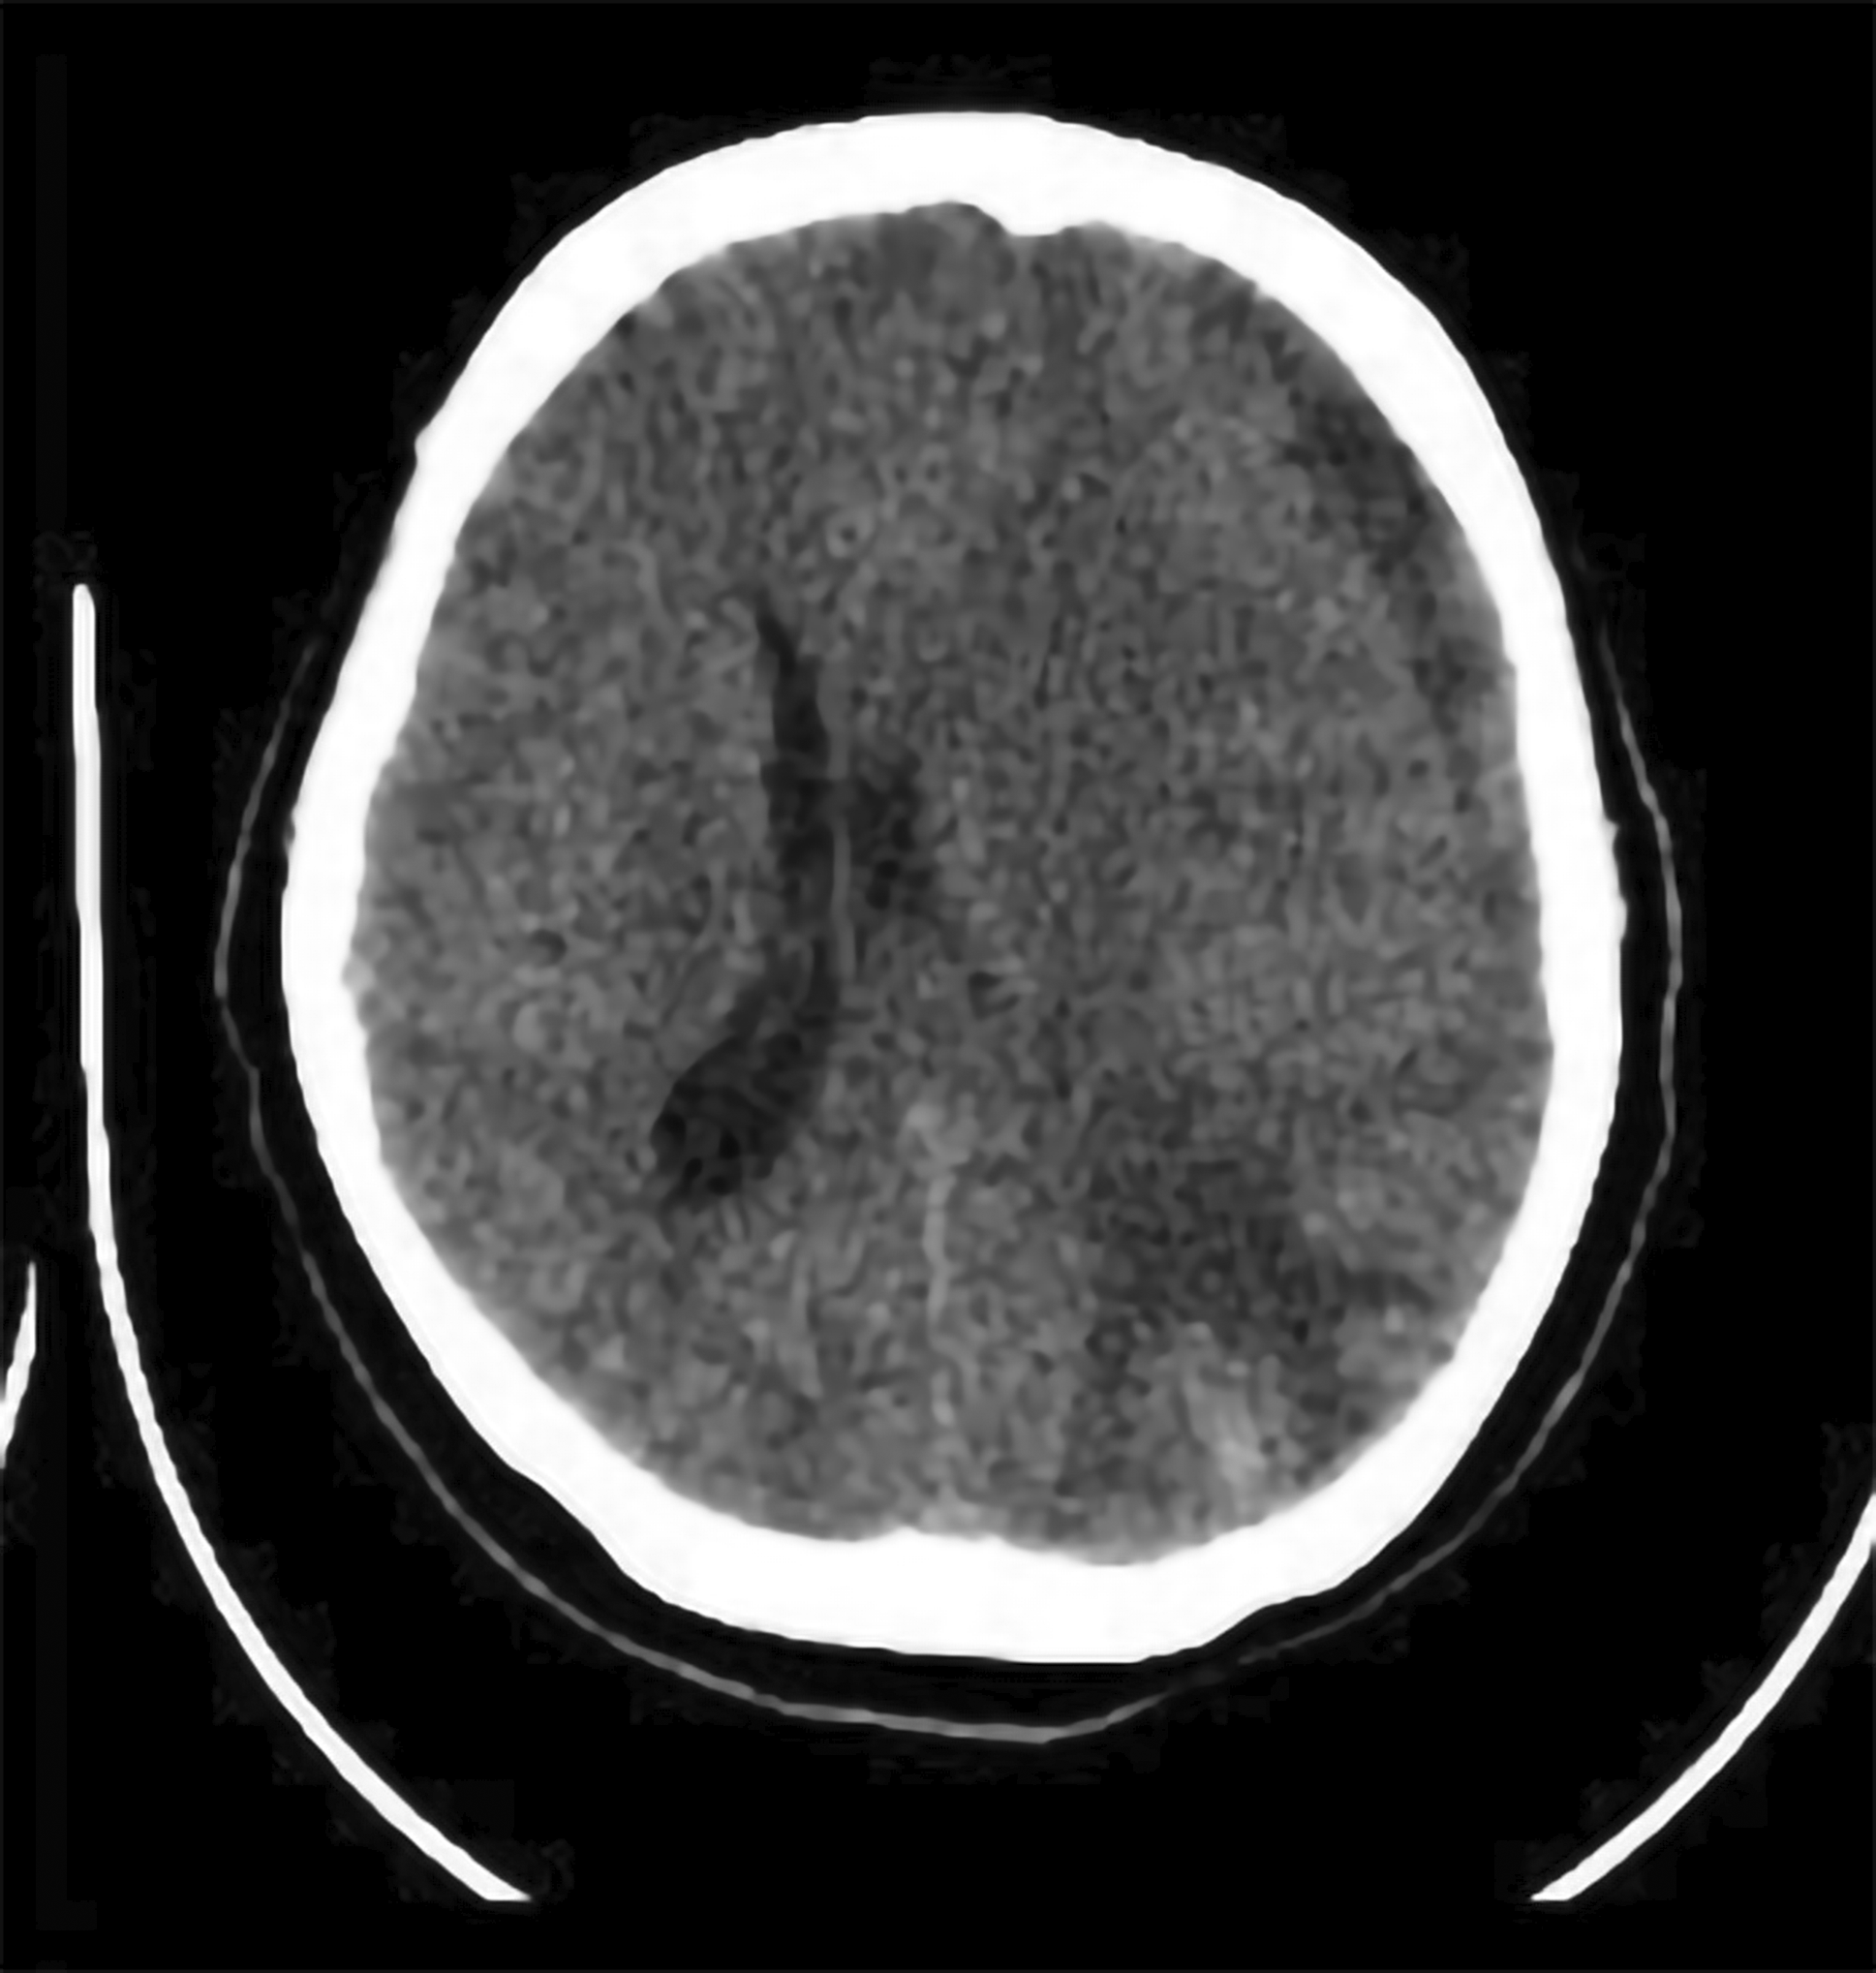

An emergency non-contrast head CT scan was performed immediately following the neurological decline. This revealed a remote haemorrhagic event, distant from the original operative site. The findings included a 20cc left parietal intracerebral haematoma and a concomitant acute left frontoparietal subdural haematoma. The combined mass effect resulted in a midline shift of over 5 mm ( Figure 4).

Medical therapy to control intracranial pressure (ICP) was initiated, consisting of intravenous mannitol and head-of-bed elevation. Following this conservative management, her level of consciousness progressively improved over the next three days. However, the patient suddenly became aphasic and could not understand any command on day 13th postoperatively ( Figure 5). Another head CT scan was performed and revealed partially resolved ICH at the parietal lobe with slight additional thickness of subacute SDH and midline shift to the right. Conservative management with mannitol and tranexamic acid was continued. The patient showed clinical improvement after 2 days and discharged from hospital at day 18th postoperatively. The three-month postoperative MRI confirmed gross total resection of the meningioma and complete resolution of the remote haemorrhage, without evidence of any vascular malformation ( Figure 6).